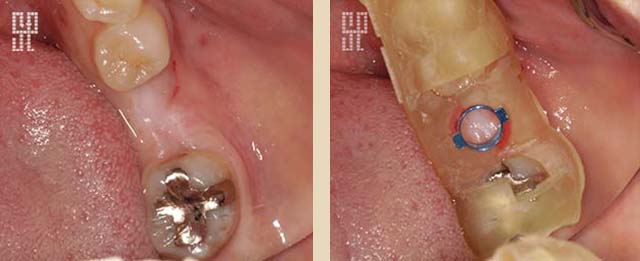

インプラントの構造は図のように、上部構造・アバットメント・インプラント体(人工歯根)の大きく3つの部位に分けられます。

歯を失った骨にインプラント(人工歯根)を埋め込み、その上に歯を立ち上げます。 歯の欠損が与える影響は、機能・審美・そして精神的にも大きなダメージです。インプラントは、歯の欠損における有効な治療法なのです。